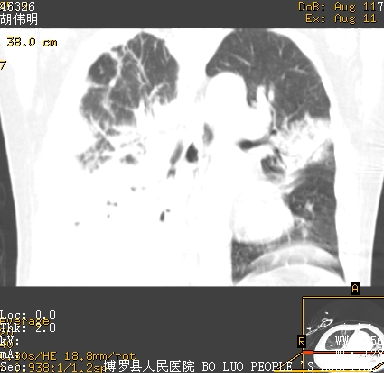

icu病人,几天都没明确诊断。m,76y,咳嗽、咳痰1周,伴气促,右胸痛入院,pe:t38.3c p135 r25 bp135/85。双肺可闻及大量湿罗音,心、腹未见明显异常。诊断:1心衰?2肺部感染?3冠心病?

11号ct

双肺感染性病变,下叶膨胀不全,胸水,左室大。

1)两肺感染性病变(右肺下叶肺脓肿可能)。2)双侧胸腔积液,以右侧为甚。

ards,肺感染性病变,右下叶实变,双侧胸腔积液,右侧为著,叶间胸膜积液,右上肺陈旧性tb纤维灶,左室大。